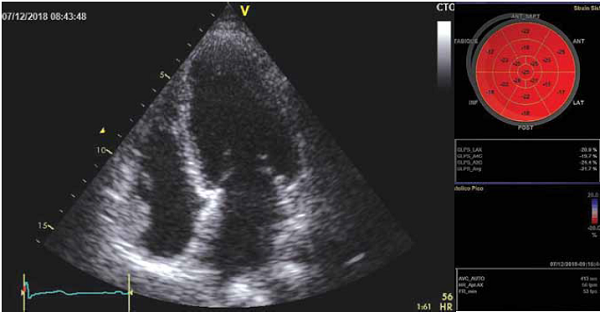

El ecocardiograma mostró una función sistólica moderadamente deprimida con una fracción de eyección del 39%, severa hipoquinesia no cicatrizal del ápex con strain marcadamente disminuido en región apical, compatible con cardiopatía de Tako-tsubo (Figura 2).

Se realizó seguimiento post-alta con ecocardiograma a los 30 días, que mostró normalización de la función ventricular y del strain, sin trastornos de la motilidad (Figura 4). No obstante, el ECG persistió con QT prolongado, sin constatarse nuevos episodios de arritmia ventricular ni recurrencia de síncope.